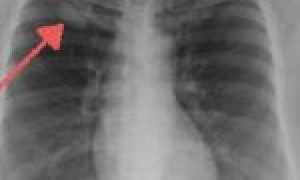

- Аденокарцинома легкого. Чаще всего эта разновидность заболевания развивается у людей, которые курят. Опухоли развиваются в виде узла или имеют форму дерева. Опухоль легких стелящегося характера развивается с полиферацией вдоль поверхности интактных стенок альвеол и не имеет признаков инвазии стромы или сосудов. Если опухоль обнаруживают на 2-3 стадии, то ее лечение эффективно в 40-60% случаев.